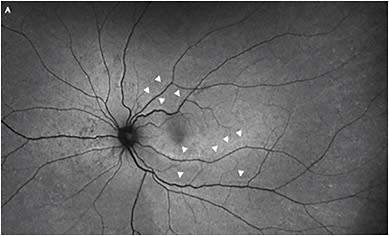

In minimal gas vitrectomy (MGV), air fluid exchange is completely avoided and a small expansile bubble of 0.6cc of pure SF6 gas is injected at the completion of surgery.3

The patient positions similar to how they would for PnR, and the retina reattaches naturally by the action of the RPE pump. This is likely to lead to a better integrity of reattachment compared with standard PPV with a full gas fill in terms of retinal displacement (LIRA/HIRA) (Figure 2).